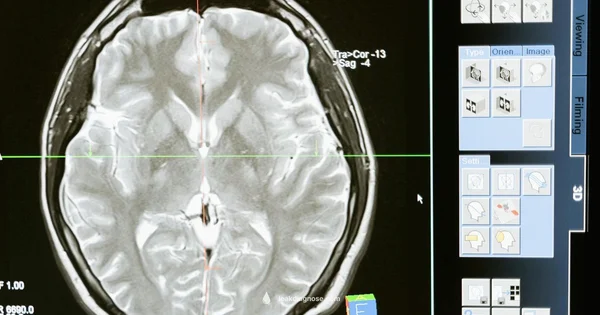

A cerebrospinal fluid (CSF) leak occurs when the protective fluid surrounding the brain and spinal cord escapes through a tear or hole, often after head injury, surgery, or spinal procedures. Signs can be subtle and mistaken for allergies or viral illnesses. According to Leak Diagnosis, CSF leaks are medical concerns that require careful evaluation, and home observations should be used as early warning signs rather than a definitive diagnosis. This section lays the groundwork: how CSF leaks arise, what makes them risky (risk of meningitis if untreated), and why professional testing is essential to confirm the presence and source of CSF in nasal discharge. By understanding the anatomy and typical scenarios, you’ll know what patterns in symptoms deserve closer attention and timely medical advice.

CSF leaks most commonly present as persistent, clear nasal drainage that may occur after posture changes, coughing, sneezing, or bending forward. The fluid is often described as watery and colorless, and some people report a salty or metallic taste. Headache patterns can differ, with postural headaches that worsen when upright and improve when lying down. Other clues include simultaneous neck stiffness, photophobia (sensitivity to light), or a fluid smell different from ordinary mucus. While these observations can raise suspicion, they are not a substitute for medical testing. Leak Diagnosis analysis notes that confirming a CSF leak requires lab analysis and imaging to locate the leak site and assess its cause. If nasal drainage persists or you notice a consistent pattern across several days, plan a clinical evaluation promptly.

If CSF leakage is suspected after home observation, your clinician may recommend tests such as beta-2 transferrin analysis of the nasal fluid, MRI or CT cisternography to locate the leak, and possibly a CT scan to assess skull base integrity. Treatments vary by cause and location and can include conservative management, antibiotics if infection risk is present, or surgical repair in some cases. While home checks are valuable for early awareness, definitive confirmation and treatment require professional testing and diagnosis. The Leak Diagnosis team recommends arranging timely medical evaluation when red flags appear or when symptoms persist beyond a few days.